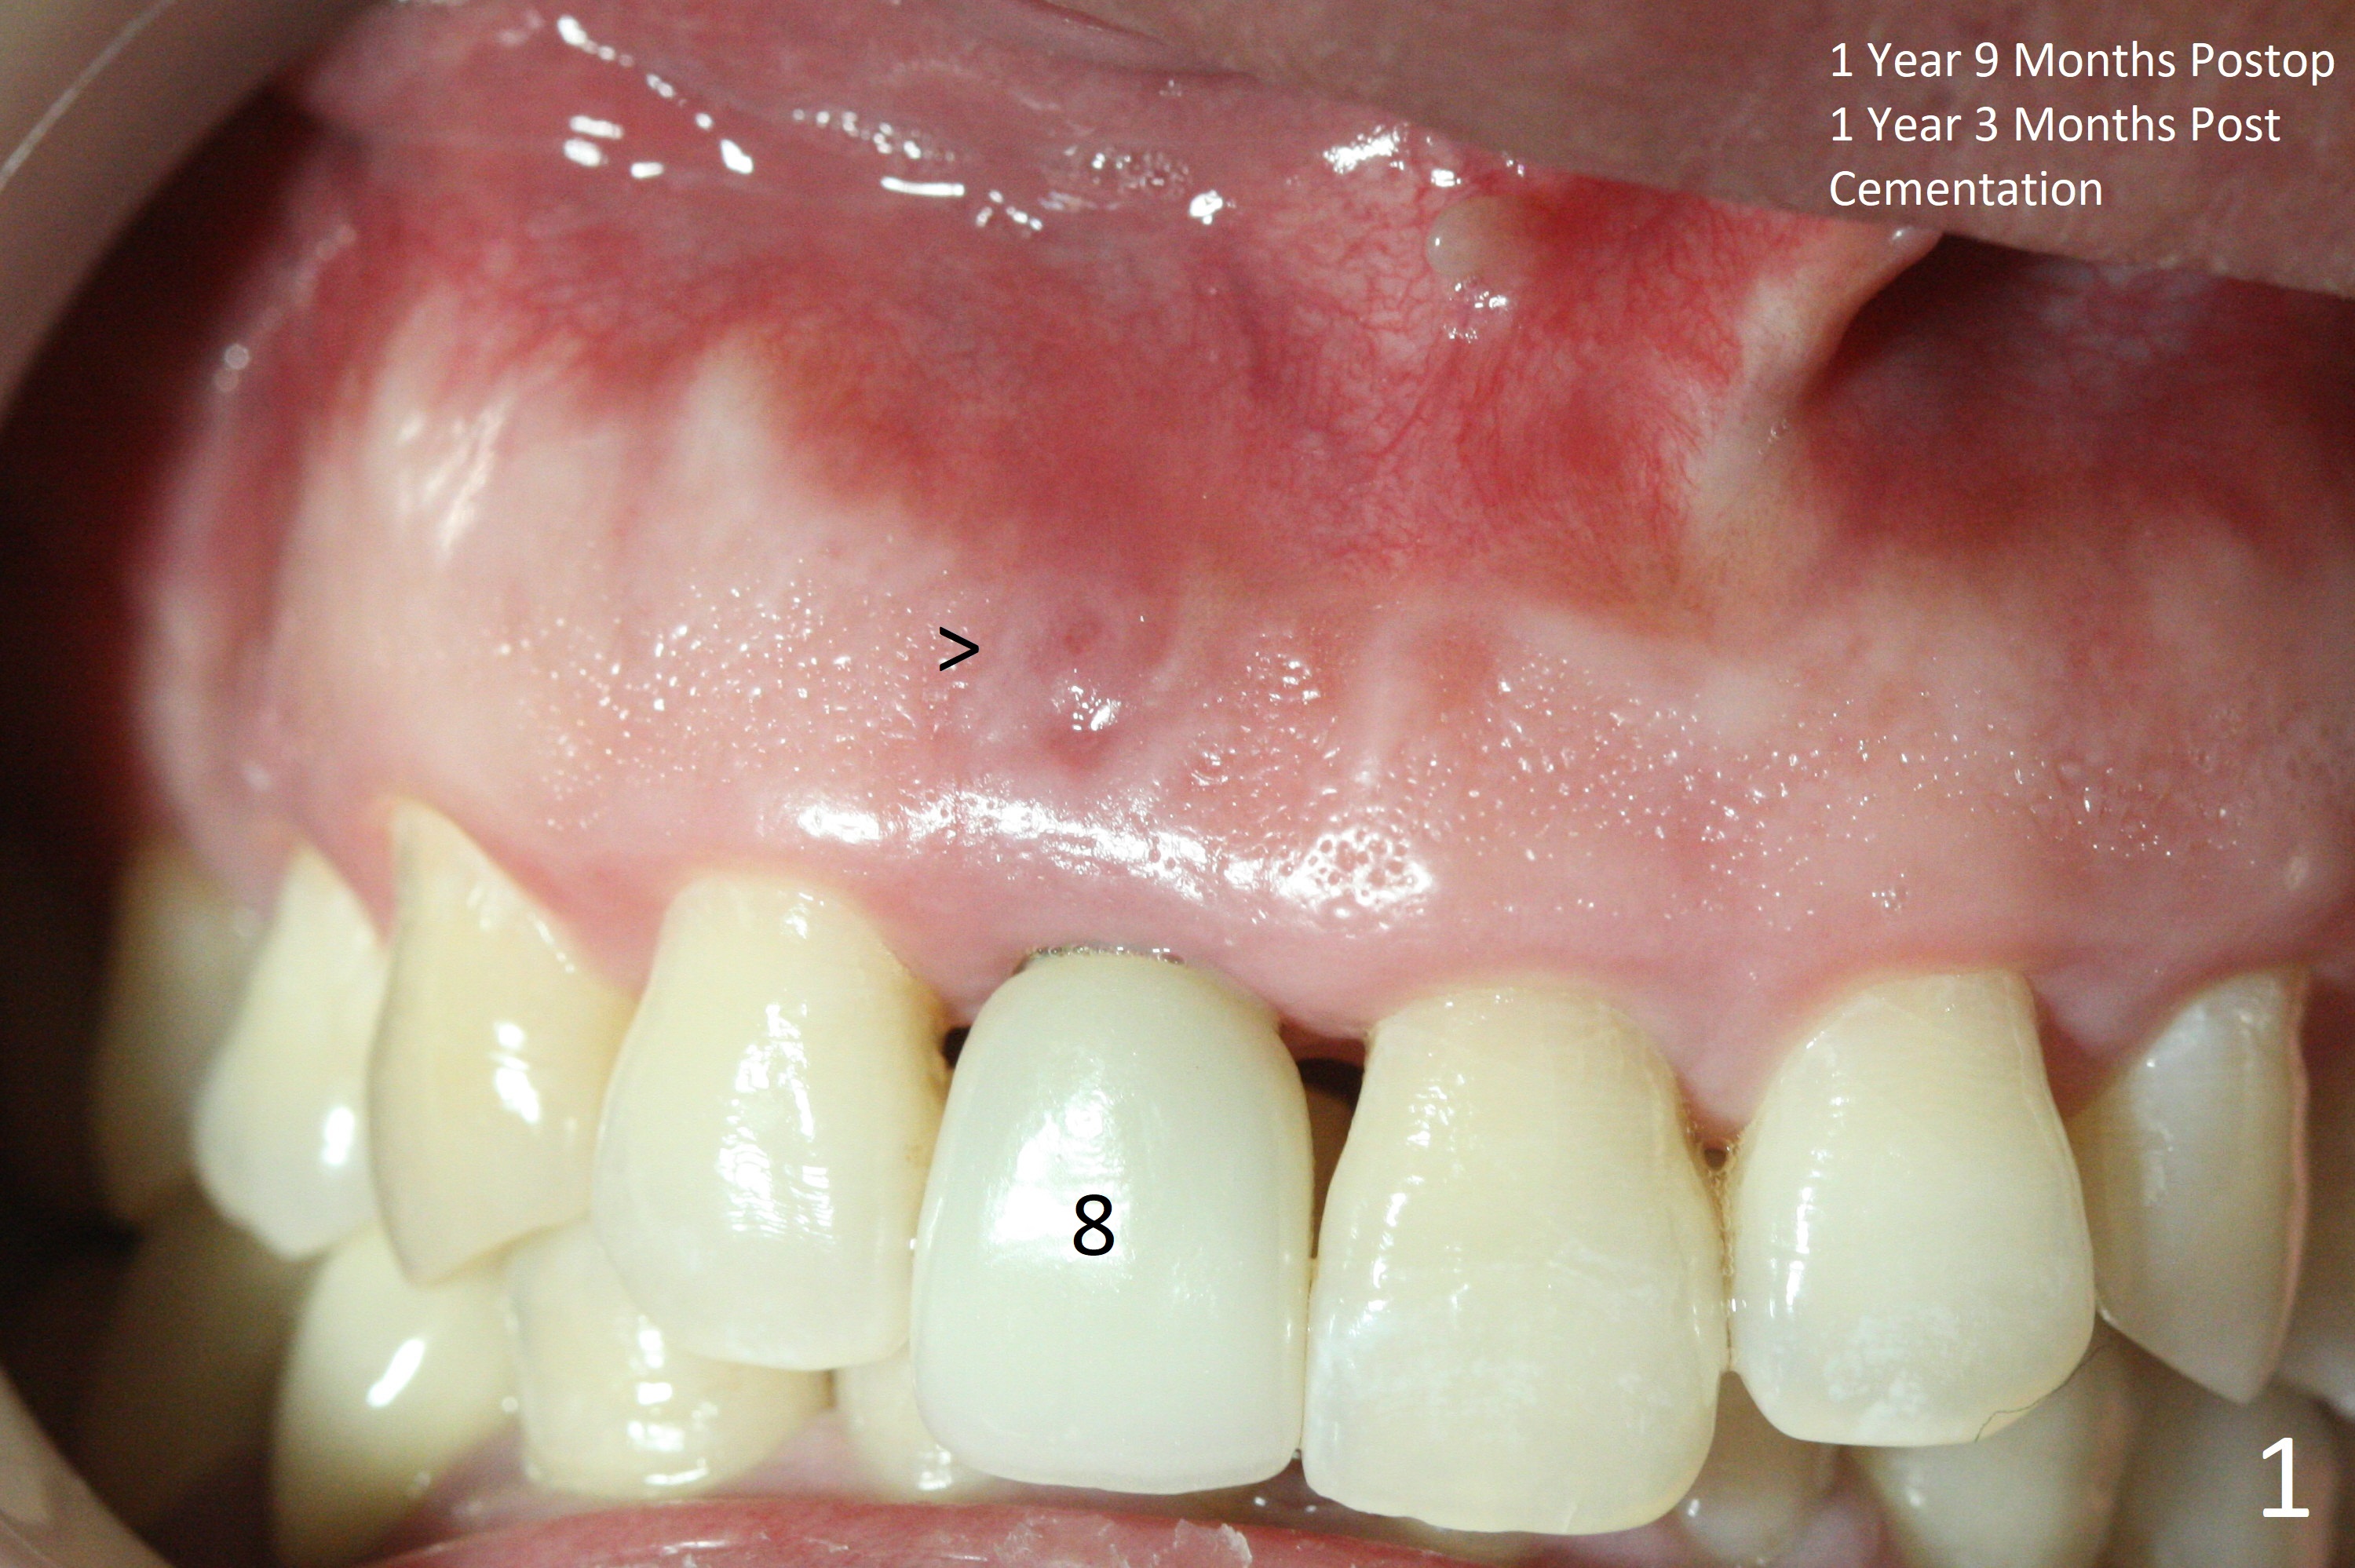

The patient returns because of purulent exudate from the buccal fistula (Fig.1 *) 1 year 9 months postop (1 year 3 months post cementation). Preop CT shows buccal thread exposure (Fig.2 arrowheads). To prevent postop gingival recession, a semilunar incision is made between the fistula and the gingival margin (Fig.3). After removal of granulation tissue (Fig.4), allograft in sticky bone form is packed (Fig.5). Following placement of PRF membrane and 6-month collagen membrane, the wound is closed (Fig.6). Since the implant (Fig.7 I) thread exposure is within bone (B) boundary (Fig.8 red dashed line), bone graft with PRF should be able to take care of periimplantitis (A: abutment). To prevent periimplantitis in similar situation, the immediate implant should be placed deep (not necessarily long, 18 mm) and narrower (3.5 mm instead of 3.8 mm). The defective buccal plate should be repaired with sticky bone and collagen membrane with incision if necessary. The wound does not dehisce 1 week postop (Fig.9) or 3 weeks postop (Fig.10, immediately post suture removal). Although bone graft seems to stay in place 6 months postop (Fig.11,12), the patient complains of bone graft expulsion sometimes. The buccal gingiva has deficiency (Fig.13). To fix it, make a remote incision (Fig.14 black line) and dissect before gingiva graft (Fig.15 dashed line). After removal of crown/abutment, the sinus track and implant surface are treated with Waterlase. A shorter cuff abutment is placed (4.5x5(4 to 3) mm) with a new provisional. The patient feels better with reduced sinus track 2 weeks postop (Fig.16).